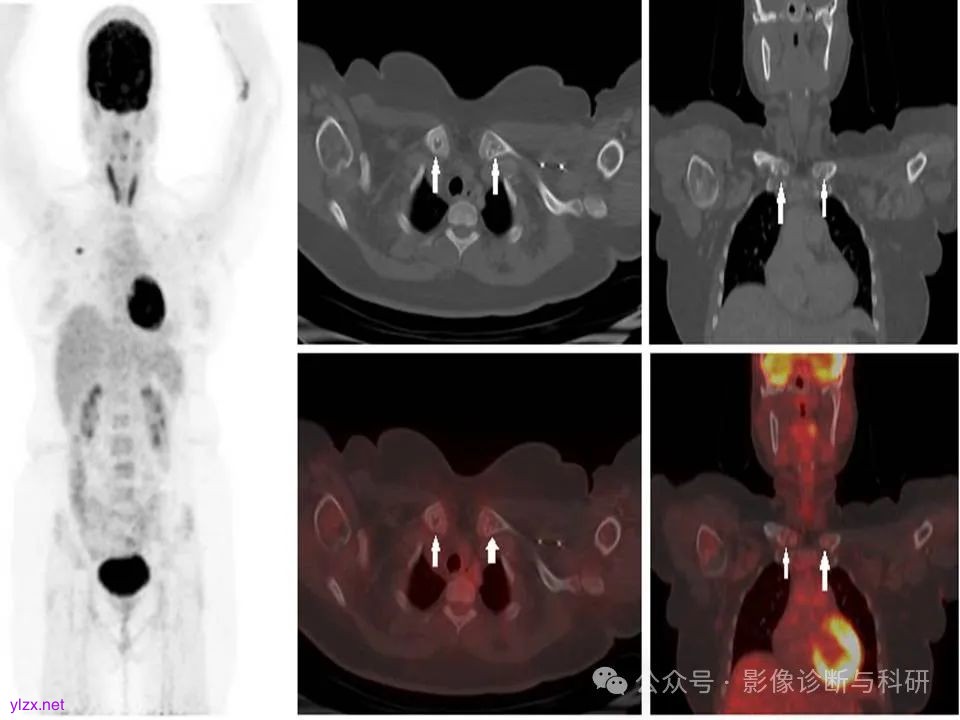

40岁,女性,新近诊断为右乳癌,行F-18 FDG PET CT分期。显示右乳上内侧象限有 FDG 高代谢病变。此外,在锁骨中还发现了以下发现(白色箭头),代谢无增高,为菱形窝结构。